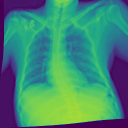

4.1.2 Lung Segmentation

Additionally, we evaluate the performance of DiffeoNN on real-world data, using a dataset with chest X-ray images and their ground-truth lung segmentation from (RSUA, 2023). The original dataset contains images and corresponding ground-truth segmentations into three different classes (“Non-Covid”, “Covid”, and “Non-Covid-Pneumonia”). We combine the images and corresponding ground-truth segmentations of the initial three classes into one dataset, which is then split into a training dataset of image-segmentation pairs, a validation dataset of pairs, and a test dataset of pairs. We then proceed as in Section 4.1.1 to create a dataset of diffeomorphically transformed images.

Benchmarking Results

We apply DiffeoNN, the inner U-Net (naïve approach) and an augmented U-Net, which is trained on the original and the diffeomorphically transformed training dataset, to the diffeomorphically transformed images from the test dataset. Visual results are presented in Figure 4 and further details on the experimental setup, training, and additional examples in Appendix B. The results closely mirror those obtained on the synthetic dataset, see Table 1(b). On average, DiffeoNN outperforms the naïve approach, validating the effectiveness of our approach. The canonicalisation step pushes the input image towards the training dataset by moving the thorax to a more central position and aligning the shoulders, which makes it easier for the inner U-Net to predict an accurate lung segmentation. While our method performs slightly below the augmented gold-standard baseline, it offers more flexibility by not relying on data augmentation or retraining, making it a practical and robust solution in real-world applications.